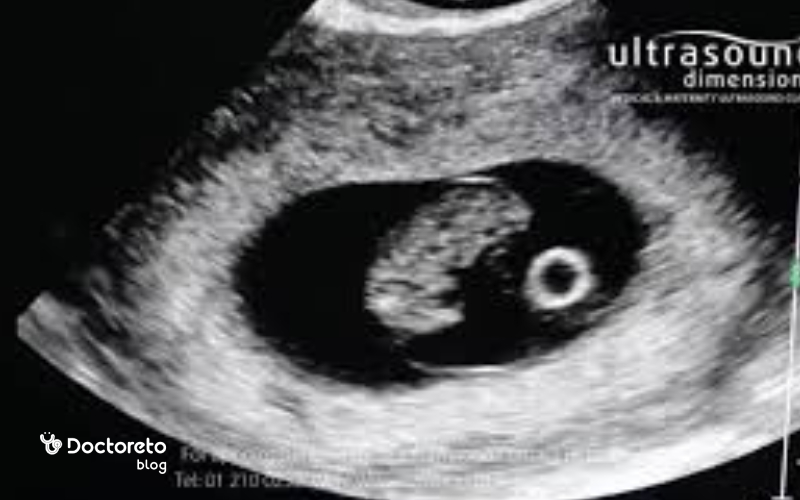

سونوگرافی در هفته هشتم بارداری

اگر در هفته قبل سونوگرافی انجام ندادهاید، ممکن است پزشک برای هفته هشتم حاملگی سونوگرافی را تجویز کند. در سونوگرافی میتوانید صدای ضربان قلب جنین را بشنوید. تصویر جنین شبیه به یک لوبیا دیده میشود. هنوز برای تشخیص جنسیت از طریق سونوگرافی زود است.

ضربان قلب جنین در هفته هشتم

در هفته هشتم بارداری، قلب جنین بهطور کامل شروع به تپیدن کرده و ضربان آن در سونوگرافی قابل مشاهده است. در این مرحله، تعداد ضربان قلب جنین معمولاً بین ۱۱۰ تا ۱۶۰ ضربه در دقیقه است، اما در برخی موارد ممکن است کمی بالاتر نیز باشد و همچنان طبیعی تلقی شود. در اوایل بارداری، قلب جنین با سرعت بیشتری میتپد تا اکسیژن و مواد مغذی لازم برای رشد سریع اندامها را تأمین کند. مشاهده ضربان قلب در سونوگرافی نشانهای مثبت از رشد سالم جنین است و یکی از مهمترین معیارهای ارزیابی زنده بودن بارداری محسوب میشود. اگر در این هفته ضربان دیده نشود، پزشک معمولاً یک سونوگرافی تکراری پس از یک تا دو هفته تجویز میکند تا اطمینان حاصل شود که بارداری بهدرستی در حال پیشرفت است.

در هفته هشتم بارداری، معمولاً ضربان قلب جنین در سونوگرافی قابل مشاهده است و نشانهای از رشد طبیعی او بهشمار میرود. بااینحال، اگر در این هفته ضربان دیده نشود، هنوز جای نگرانی نیست، زیرا ممکن است تخمکگذاری دیرتر، خطای محاسبه سن بارداری یا رشد آهسته جنین باعث این تأخیر شده باشد. در چنین شرایطی، پزشک معمولاً سونوگرافی را یک تا دو هفته بعد تکرار میکند تا وضعیت بهصورت دقیق ارزیابی شود. اگر پس از آن هم ضربان قلب وجود نداشته باشد، احتمال سقط فراموششده (missed abortion) مطرح میشود و نیاز به بررسیهای بیشتر دارد؛ اما در بسیاری از موارد، ضربان در سونوگرافی بعدی ظاهر میشود و بارداری روند طبیعی خود را ادامه میدهد.